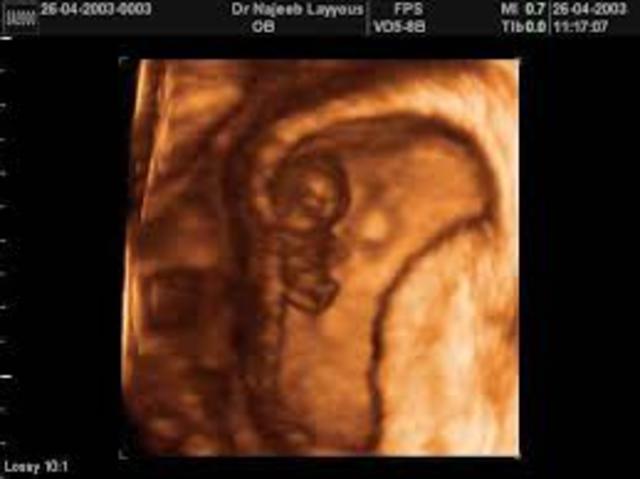

~ First ultrasound scan

~ Mom can learn the sex of the baby.

~ First look at the baby

~ Starts to feel a connection to the baby